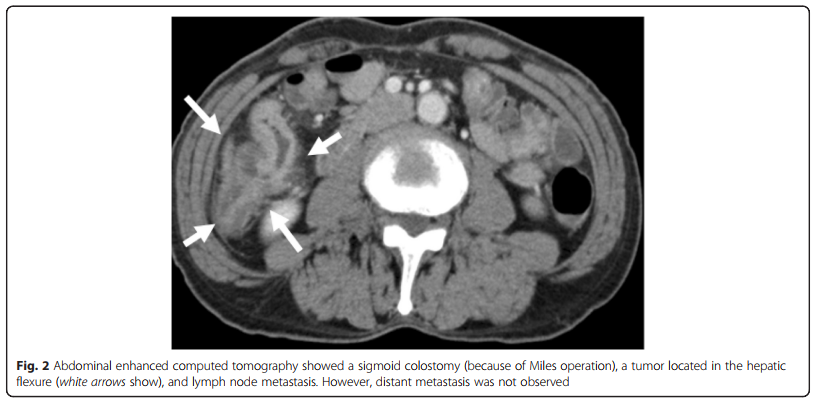

The hepatic flexure colon cancer is seen.

Below is a 3D reconstructed screen. Due to the cancer, the colon is narrow.

The example of splenic flexure colon cancer detected by CT colonography.